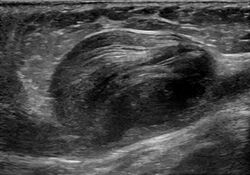

Ultrasonography of an aneurysm of the great saphenous vein due to venous valve insufficiency.

- Arterial and venous, with arterial being more common.[8]